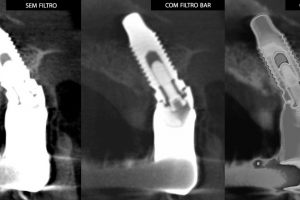

Entre os produtos oferecidos pela CDT Software é o E-VOL DX, reconhecido por pesquisas acadêmicas nacionais e internacionais de odontologia, possibilita imagens mais nítidas e com maior riqueza de detalhes! “O e-Vol DX é um software que supre demanda dos tradicionais aparelhos de radiologia. Compatível com os principais equipamentos do mercado, ele é composto por filtros e ferramentas que transformarão seus laudos”, ressalta.

Além disso, o e-Vol DX está em constante atualização para atender e antecipar-se às demandas dos profissionais da área de radiologia odontológica. Por isso, é um investimento seguro e eficaz e que não estará defasado. Com todos os recursos que garantem obter as melhores imagens de seu tomógrafo, o e-Vol DX possibilita otimizar o tempo de produção com o uso de ferramentas exclusivas.